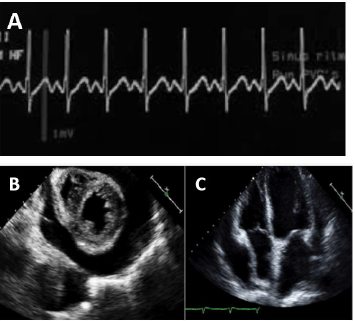

Homem de 64 anos, hipertenso e dislipidêmico, foi submetido à coronariografia eletiva via artéria radial direita, devido à angina progressiva aos esforços, refratária ao tratamento medicamentoso. Estava em uso de aspirina, atorvastatina, atenolol, anlodipina e mononitrato de isossorbida. O exame revelou duas lesões calcificadas de 80% no terço médio da artéria descendente anterior e 70% na região proximal da coronária direita. Foi submetido, no mesmo momento, à angioplastia com implante de 1 stent farmacológico em cada lesão. Duas horas após chegar na unidade cardiointensiva, o paciente evoluiu com rebaixamento do nível de consciência, palidez cutânea e PA: 78x40 mmHg.

O registro do ECG no monitor (A) e o ecocardiograma de urgência na beira do leito (B e C) estão dispostos a seguir.

Após reposição volêmica e início de vasopressores, houve melhora do nível de consciência e da pressão arterial (96x60 mmHg).

A conduta terapêutica mais indicada nesse momento seria